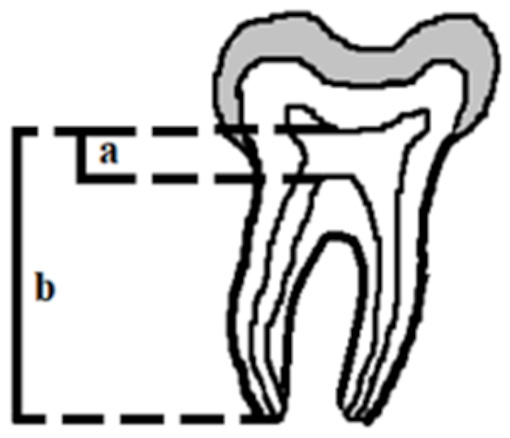

There are several ways to diagnose taurodontism. In 1928, Shaw classified the subtypes of this disease as hypo-, meso- and hypertaurodontism, based on the relative shift of the pulpal floor. This subjective assessment has often led to a misdiagnosis of this anomaly.4 In 1978, Shifman and Chanannel (Figure 4), and later Kim Seow and Lai (Figure 5), developed taurodontal indices in order to determine the occurrence of taurodontism and classify it based on a biometric study, as shown radiographically (Figure 2, Figure 3).3 Determining taurodontism consists of dividing the distance between the lowest point of the pulp chamber roof and the highest point of the pulpal floor by the distance between the lowest point of the pulp chamber roof and the apex, and then multiplying the result by 100. When this value is equal to or greater than 20, the patient is said to have a taurodont tooth. Values from 20 to 29.9 classify the tooth as a hypotaurodont, values from 30 to 39.9 classify it as a mesotaurodont, and values from 40 to 75 identify it as a hypertaurodont. The 2nd index used to identify taurodontism calculates the crown-to-root ratio of the tooth. This is accomplished by measuring the distance from the deeper furrow on the occlusal surface of the furcation and comparing it to the distance from the furcation to the apex. A result from 1.1 to 1.29 indicates hypotaurodontism, from 1.3 to 2.0 indicates mesotaurodontism and above 2.0 indicates hypertaurodontism.3, 13